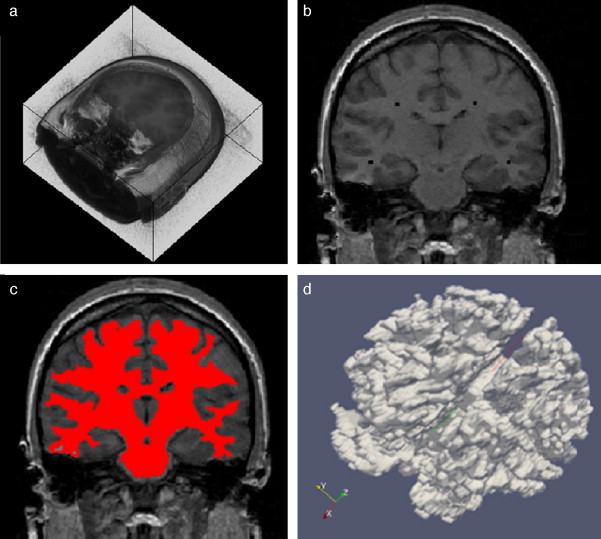

En la figura 10 se presenta el resultado de segmentar la materia blanca del cerebro en IRM empleando la rutina de Region Growing mencionada. En la figura 10 .a se observa la vista 3D del volumen inicial. En la figura 10 .b se observa uno de los cortes de la figura 10 .a con la selección de cuatro semillas iniciales de forma esférica dentro de la zona de la materia blanca. En la figura 10 .c se observa en color rojo la zona región de la materia blanca obtenida al finalizar la rutina de segmentación. En la figura 10 .d se presenta una vista 3D de la zona de la materia blanca segmentada.

|

Figura 10. Segmentación de materia blanca empleando Region Growing en IRM del cerebro. (a) Volumen formado por varios cortes de IRM cerebral original. (b) Vista de un corte coronal con la lección de cuatro semillas iniciales. (c) Vista del corte coronal (b) con la materia blanca segmentada con Region Growing . (d). Vista volumétrica de la materia blanca segmentada en (c). |